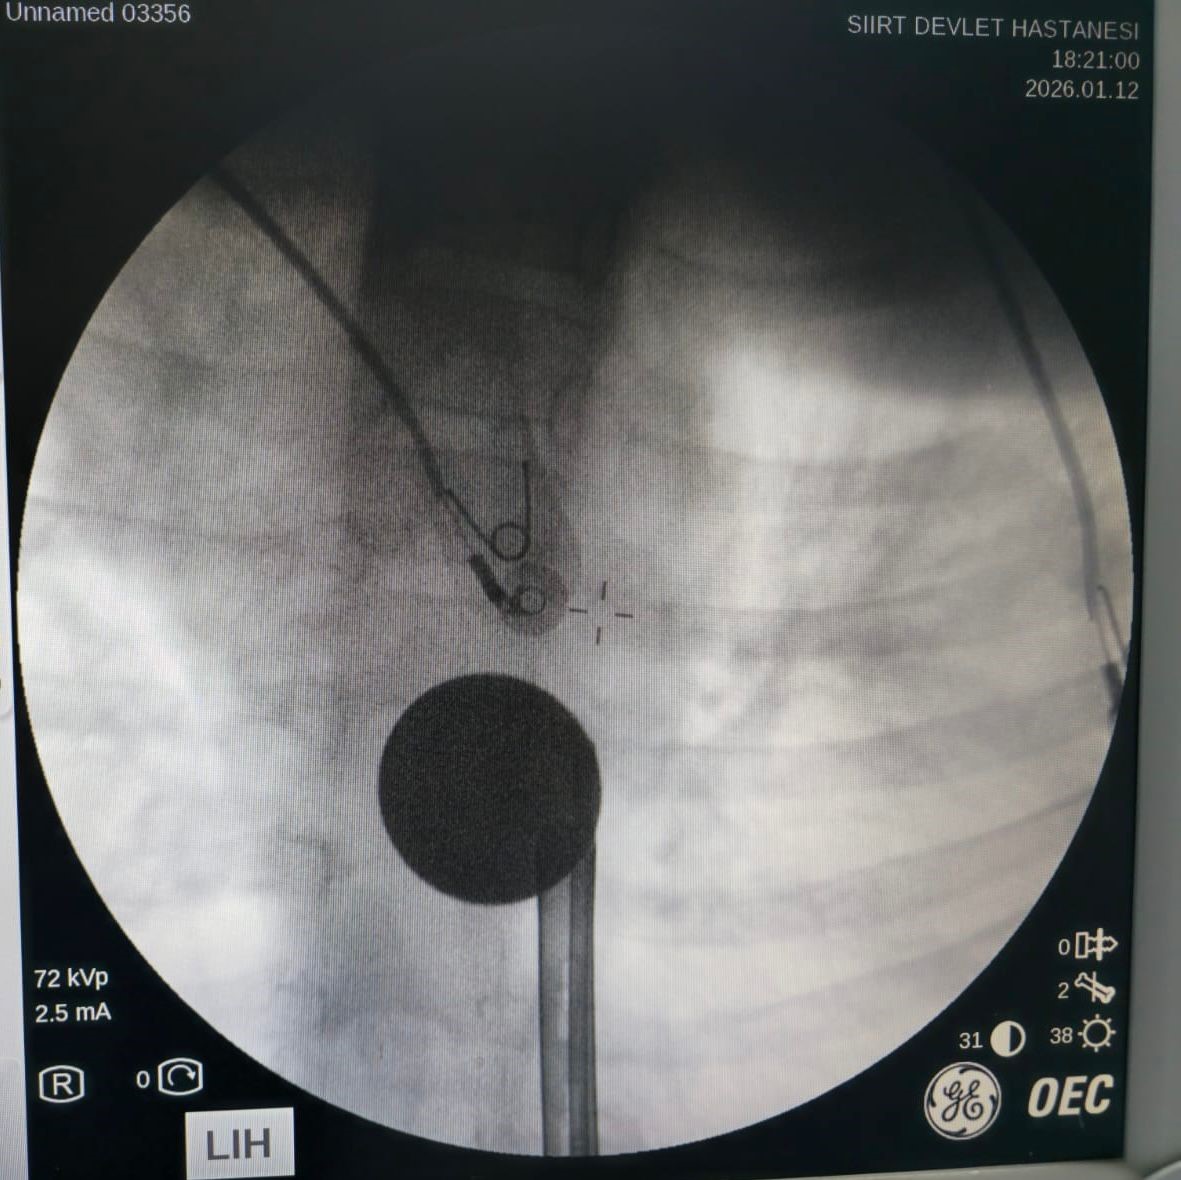

Yabancı cisim yutma şikayetiyle ailesi tarafından Siirt Eğitim ve Araştırma Hastanesine getirilen 8 yaşındaki Y.K.'ya yapılan ilk değerlendirme ve görüntüleme tetkiklerinin ardından ilgili branşlar tarafından operasyona alındı. Y.K.'nın yemek borusuna kadar ilerlediği tespit edilen madeni para, Gastroenteroloji Uzmanı Dr. Yaren Dirik ve Kulak Burun Boğaz (KBB) Hekimi Dr. Yasin Gökçınar tarafından endoskopik yöntemle çıkartıldı.

"Yaptığınız ön tetkiklerde kulak burun boğazla birlikte değerlendirdiğimizde paranın yemek borusuyla ağız tabanı arasında, KBB'nin hem de gastroenteolojinin ortak girişiyle yapabileceği bir alanda olduğunu tespit ettik. Tespitten sonra KBB ile istişarede bulunduk. Ortaklaşa işleme aldık ve madeni 5 lirayı ameliyatsız bir şekilde endoskopik olarak çıkardık"